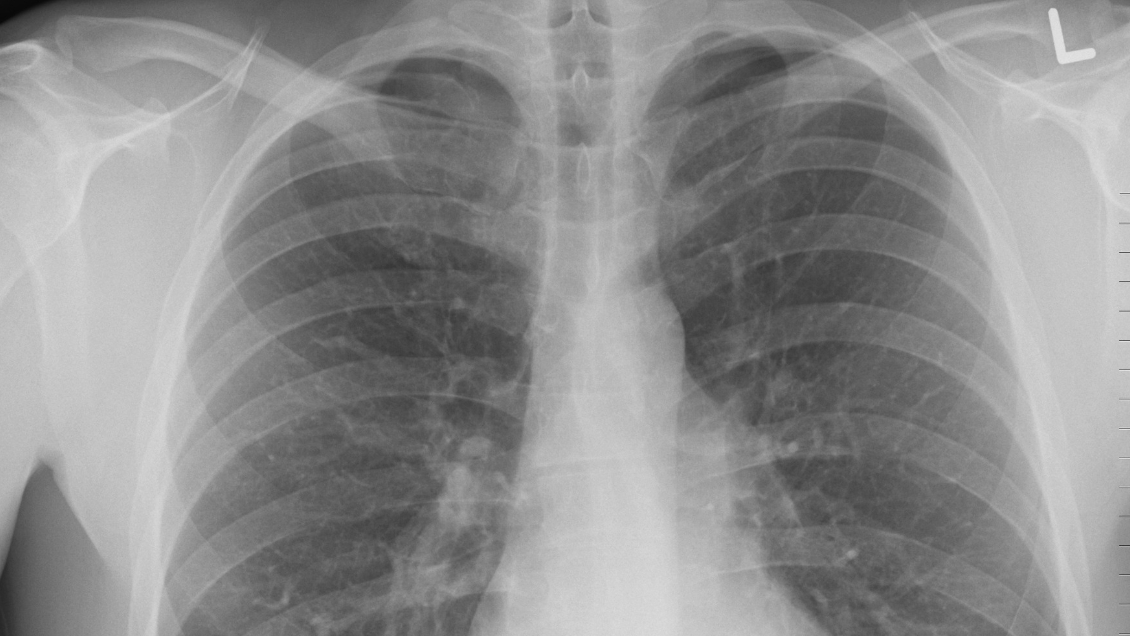

Tras realizarle una radiografía en el tórax, los médicos confirmaron la fractura de cuatro costillas y le aseguraron a Huang que la causa principal del incidente fue por su bajo peso corporal. Con una altura de 171 cm y un peso de 57 kg, el médico aseguró que "sus costillas se pueden ver claramente debajo de su piel" y que "no hay músculo para sostener el hueso, por lo que es fácil que sus costillas se fracturen al toser".